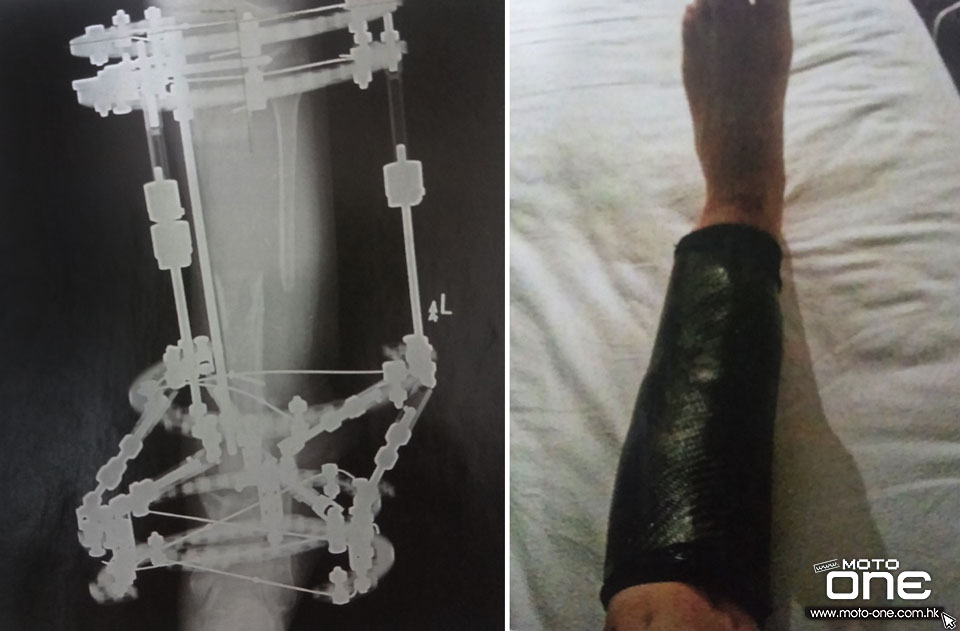

●從X光可看見折斷的小腿骨。

●2012年初,赫徹臣出席電單車活動時造成骨折,並發生細菌感染,導致骨頭無法增生,因此接受植骨手術(Bone Transportation),醫生把10cm的骨頭鋸走,然後安裝像機械人穩定架固定沒有骨頭的小腿,讓骨頭以每月1cm自然增生。

●為了參加2012年NORTH WEST 200及TT人島,赫徹臣自製碳纖腳套固定小腿位置。

在英國接受連串練習後,赫徹臣迅速習慣新的轉檔系統,從數據也可看到與過去的轉檔速度無異,而艱苦的體能訓練還協助他取得2011澳門格電季軍(冠軍路達,亞軍謝索普)。可是惡運再次降臨赫徹臣身上,2012年2月出席電單車活動時,在操練越野車期間跌斷舊患,與此同時發生細菌感染,由於骨折位置無法自然癒合,赫徹臣說當時接受名為植骨手術(Bone Transportation),醫生鋸走10cm受細菌感染骨頭後,安裝了像機械人的穩定架,讓骨頭增生。